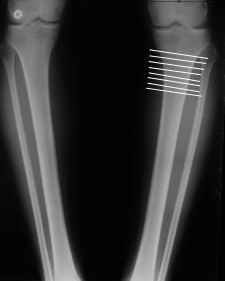

Судя по снимку у девушки имеется внутренняя установка надколенников...

Как у нее с торсионным статусом? Бедро? Голень? КТ? Торсиометры? А то, куда будут

смотреть надколенники после вашей коррекции - тоже существенный

косметический момент. Или не так?

AVM> Судя по снимку у девушки имеется внутренняя установка надколенников...

AVM> Как у нее с торсионным статусом? Бедро? Голень? КТ? Торсиометры?

Похоже, немного есть. Думаю пренебречь.

Мне представляется оптимальным на уровне 3-4 линии (т.е. как раз посредине отмеченной зоны). Если рассчимтываешь делать медиализацию, то параллельно суставной поверхности, иначе просто не сдвинешь без джистракции - отломки зацепятся. Если без медиализации - то вообще не имеет значения.

4. Если внимательно посмотришь на рентгенограммы, то в зоне перелома малоберцовой кости она втягиваетсмя внутрь, таким образом немного уменьшая объем тканей по внутреннему контуру. Причем чем выше - тем эффектнее. Не надо только совсем высоко лезть - там перонеус. Многих пайциенток это тоже смущает. Так что решаем проблему комплексно. На это, кстати, особо упирает Казбек Кудзаев.